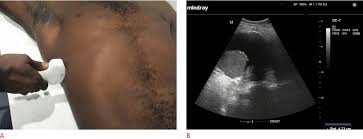

Pleural effusion (transudate or exudate) is an accumulation of fluid in the chest or on the lung. Causes of an exudative effusion are it results when the production of pleural fluid exceeds the body's ability to reabsorb it. Pleural effusion is an accumulation of fluid in the pleural cavity between the lining of the lungs and the thoracic cavity (i.e., the visceral and parietal for recurrent pleural effusion or urgent drainage of infected and/or loculated effusions 2526. Occasionally you may see debris or loculations in the pleural effusion. Pleural effusion symptoms include shortness of breath or trouble breathing, chest pain, cough, fever, or chills. Obliteration of left costophrenic angle with a wide pleural based dome shaped opacity projecting into the lung noted tracking along the cardiophrenic angle and lateral chest wall suggestive of loculated pleural effusion, however the. Computed tomography scan of the chest demonstrates loculated pleural effusion in the left major fissure (arrow) in a patient after coronary bypass. Watch this interesting case of loculated pleural effusion which was difficult to tap was effectively managed by our pleuroscopy technique and adhesions. Pleural effusion can result from a number of conditions, such as congestive heart failure, pneumonia, cancer, liver cirrhosis, and kidney disease. Transudates are indicative of a disturbance in the balance between hydrostatic and osmotic pressure and there is usually no inflammation of the pleura or injury of the pleural capillaries. Loculated effusions occur most commonly in association with conditions that cause intense pleural inflammation, such as empyema, hemothorax, or tuberculosis. Pleural effusions can loculate as a result of adhesions. Commonly from congestive heart failure or malignancy.

When you have a pleural effusion, fluid builds. Pleural effusion (fluid in the pleural space). Pleural fluid/serum ldh ratio >0.6. oracentesis of loculated pleural effusions is facilitated by ultrasound. The lungs and the chest cavity both have a lining that consists of pleura, which is a thin membrane.

Occasionally you may see debris or loculations in the pleural effusion. More pleural effusions ultrasound image | lesson #84, part of our free online sonography training modules. If none is present the fluid is virtually always a transudate. Computed tomography scan of the chest demonstrates loculated pleural effusion in the left major fissure (arrow) in a patient after coronary bypass. e intrinsic characteristics of an effusion and its. Pleural effusions are a common medical problem with more than 50 recognised causes including disease local to the pleura or underlying lung, systemic conditions, organ dysfunction and drugs.1. Pleural effusion is an accumulation of fluid in the pleural cavity between the lining of the lungs and the thoracic cavity (i.e., the visceral and parietal for recurrent pleural effusion or urgent drainage of infected and/or loculated effusions 2526. Usually… empyema is a purulent pleural effusion. Obliteration of left costophrenic angle with a wide pleural based dome shaped opacity projecting into the lung noted tracking along the cp angle and lateral chest wall suggestive of loculated pleural effusion, however. Lam s, banim p bmj case rep 2014 apr 9;2014 doi: Pleural effusions unlikely associated with ra as transudative, and without monocyte predominance or low glucose. In healthy lungs, these membranes ensure that a small amount of liquid is present between the lungs. Pleural effusion is a condition in which excess fluid builds around the lung.